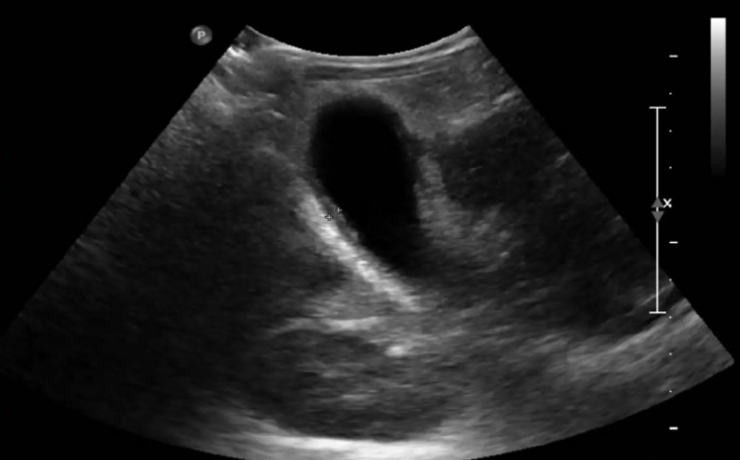

La ecografía del bazo.

La ecografía del bazo La ecografía del bazo es una parte fundamental del examen ecográfico completo, en el cual se evalúa el tamaño, forma, ubicación y parénquima del bazo, siendo necesario examinar y documentar estos aspectos detalladamente. Una de las principales ventajas de la ecografía es su amplia disponibilidad, bajo